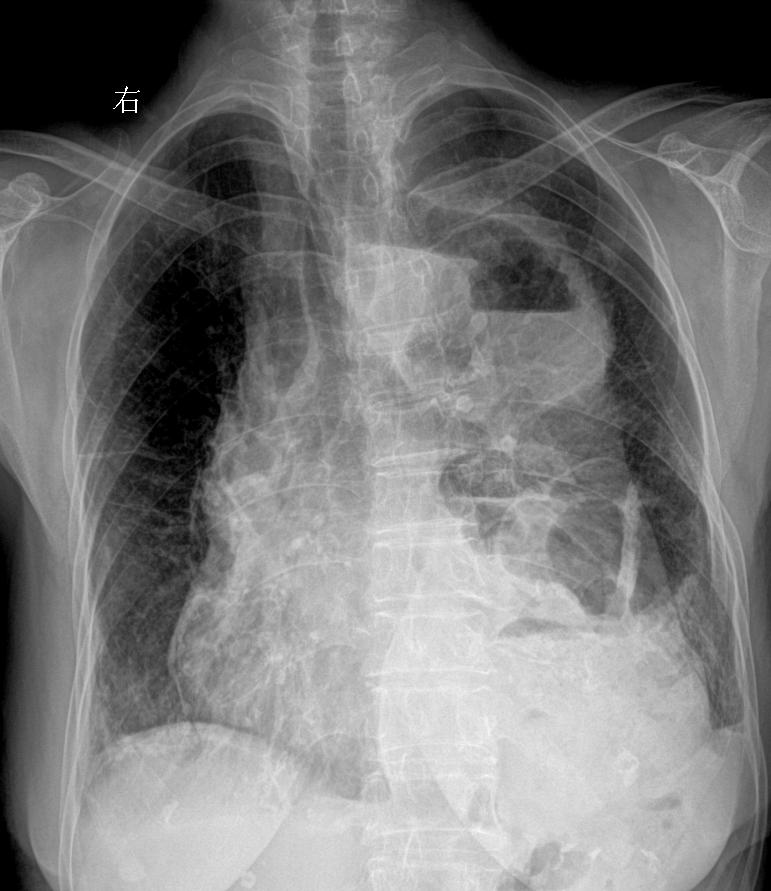

食管癌术后 胸闷就诊 女89岁